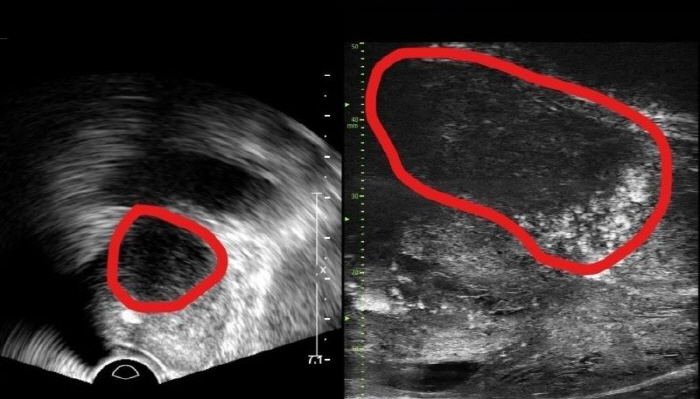

29MHz 마이크로 초음파를 사용하는 이 장비는 전립선과 주변의 해부학적 구조를 선명히 표시하고 표적 조직검사를 유도한다. 의심 영역을 실시간으로 확인하면서 전립선 조직의 미세한 변화와 병변을 식별하고 조직검사 채취를 위한 바늘을 정확한 위치에 삽입할 수 있다는 장점이 있다.

기존의 경직장 초음파는 해상도가 낮아 전립선 종양, 특히 작은 암 병변을 감지하는 데 한계가 있었다. 하지만 마이크로 초음파의 높은 해상도와 실시간 영상의 시각화는 자기공명영상(MRI)으로 발견할 수 없는 전립선암을 찾을 때도 충분히 기여할 것으로 기대하고 있다. MRI 검사 보다 환자의 신체적, 심리적, 경제적 부담도 적을 수밖에 없다.